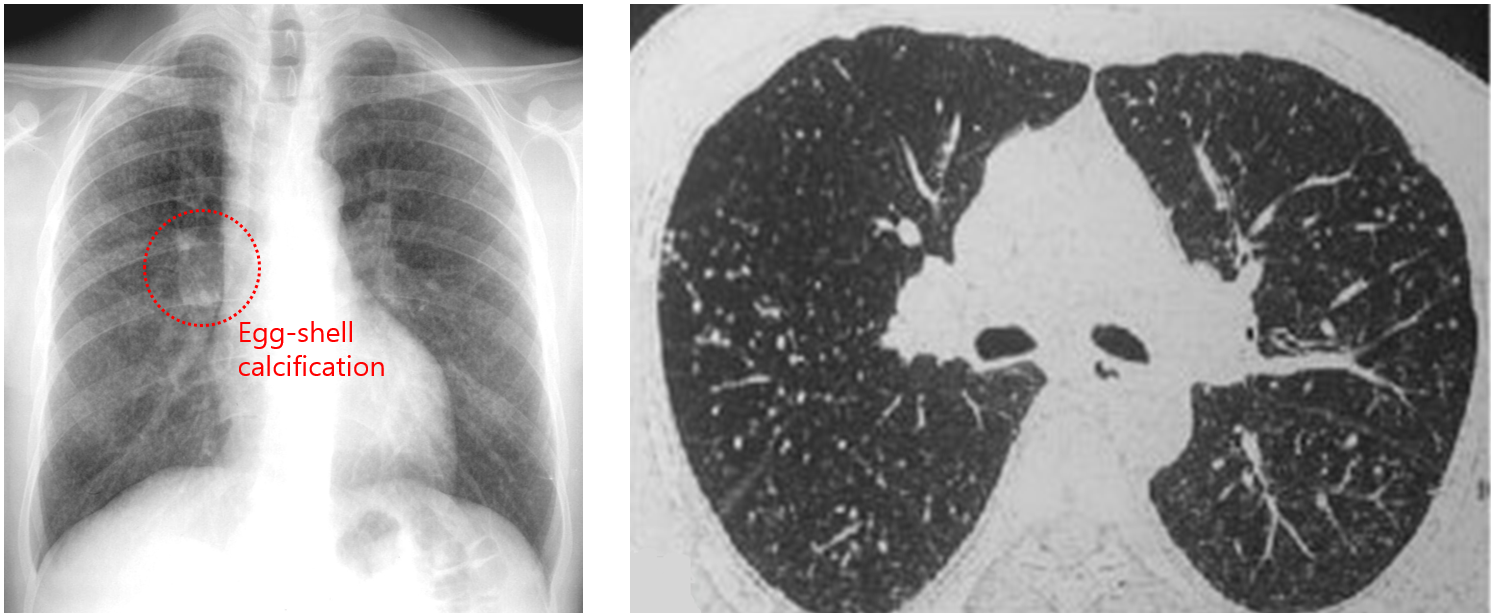

(2) CXR/CT

① 단순 규폐증: 폐 상부~중부의 small, rounded nodules (< 10 mm)

• Hilar LN 주변에 calcification 있을 수 있음 (egg-shell calcification)

② PMF: Nodule들이 서로 융합하며 불규칙한 덩이 형성 (≥ 10 mm)

3) 진단: 규소 노출력, 임상양상, 영상학적 소견으로 진단